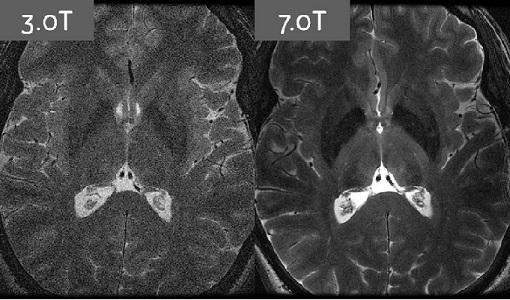

In the past years there have been many advances in imaging technologies, paving the way for the highest resolution and image quality to date. At one time, medical professionals thought that 1.5 T, and after that 3 T would be the pinnacle of MRI field strength. When 7 T was developed, nobody ever thought it could be used for anything other than research purposes. Now, several companies have taken interest in developing 7 T clinical MRI systems for use in large hospitals.

The strong suits of 7 T include neuroimaging (multiple sclerosis, peripheral nerves, hippocampus, cerebrovascular and degenerative brain diseases), musculoskeletal (cartilage, triangular fibrocartilage, osteoarthritis) and breast imaging.

It is important to remember that although there are relatively few studies directly comparing 1.5 T, 3 T and 7 T, it is generally considered that higher field strength does not necessarily mean higher diagnostic accuracy for all diseases and abnormalities. This means that 7 T MRI will fill a specific niche in the market for certain sequences and imaging methods. They include: 31P MR spectroscopy (31PMRS), which can be used as a noninvasive tool for measuring the relative intracellular concentrations of several phosphorus metabolites in different organs.